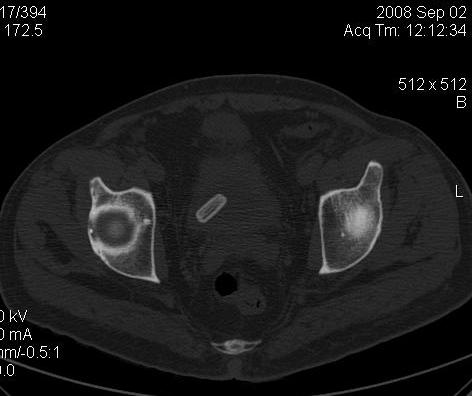

КТ Малого таза.

Что в мочевом пузыре? :?: ;)

Bladder foreign body0001.jpg

Я тоже так думал! Урологи выполнили цистоскопию, оказалось камень, такой причудливой формы.